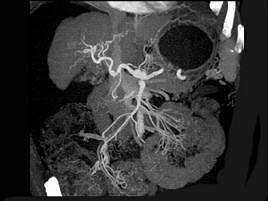

下列图像最可能的诊断是 ( )A.肝脓肿B.肝囊肿C.肝血管瘤D.原发性肝癌E.肝炎肝硬化

问题 下列图像最可能的诊断是 ( )

选项 A.肝脓肿 B.肝囊肿 C.肝血管瘤 D.原发性肝癌 E.肝炎肝硬化

答案 E